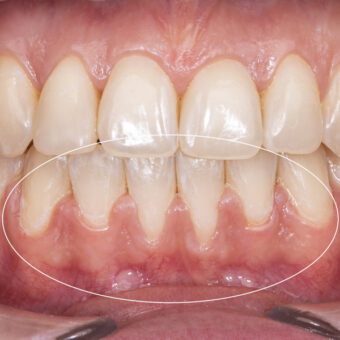

Recesja dziąsła (inaczej zanik lub cofanie się dziąseł) to proces, który odsłania korzenie zębowe, a co za tym idzie, może powodować nadwrażliwość zębów, próchnicę oraz defekt estetyczny podczas mówienia i uśmiechu.  Wśród przyczyn recesji dziąsła można wymienić m.in.: wady zgryzu, genetyczną budowę dziąseł, chorobę okluzji (bruksizm) oraz nieumiejętne szczotkowanie zębów i nieprawidłową higienę.

W SOBOTA House Of Dentistry proces leczenia recesji dziąseł poprzedzony jest zawsze wizytą ogólną i bardzo dokładną diagnozą, mającą na celu ustalenie przyczyny problemu. W zależności od źródła recesji, wybieramy odpowiednią metodę leczenia. Recesję przykrywamy własnym dziąsłem Pacjenta. Zabieg jest bardzo skuteczny, miejsce przykrycia recesji szybko się goi i nie sprawia Pacjentowi dyskomfortu.